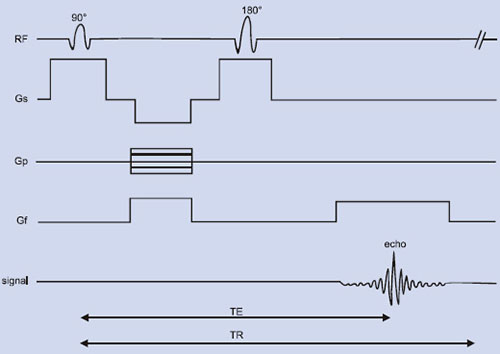

A pulse sequence is a series of timed events involving RF pulses, gradient pulses and digital sampling of an analog signal. It accomplishes two tasks: (i) to collect the data in an orderly fashion so that the origin of the signals can be determined – i.e., the pixel 10position – and this is the function of the gradient magnetic fields outlined earlier; and (ii) it influences the image contrast – pixel character – by specifying the timing and power of the RF pulses. Many of the parameters that have to be specified in a pulse sequence, such as the timing and magnitude of gradient magnetic fields are included in the computer software.

In general, MRI sequences are divided into simple building blocks that control slice selection, frequency encoding, and phase encoding of the 2D or 3D space. Hundreds of sequences exist and they all have some elements of these building blocks in common. These may be categorized into two main groups built around either the spin echo (SE) or the gradient echo (GE) and the images acquired in either a single echo or a multi-echo approach10, 19, 21. The SE pulse sequence shown in Figure 1.5 is often used in clinical diagnosis. The basic sequence of events in SE is a 90° RF pulse excitation, spatial encoding, a 180° refocusing pulse, and signal readout. The pulse sequence diagram contains several labeling conventions and in order to get images with good contrast and quality, one needs to specify (a) type of pulse sequence, (b) time intervals TR, TE, etc. (c) matrix size, (d) number of signal averages, (e) plane of image, (f) spatial separation of the slice, etc. The signal intensity, S may be given by10

Fig. 1.5: Spin echo RF pulse sequence showing the various time delays such as time of echo (TE), time of repetition (TR), etc. Gf, Gp and Gs refers to the gradient field applied along x, y and z-axes. “Echo” refers to the NMR signal (FID).